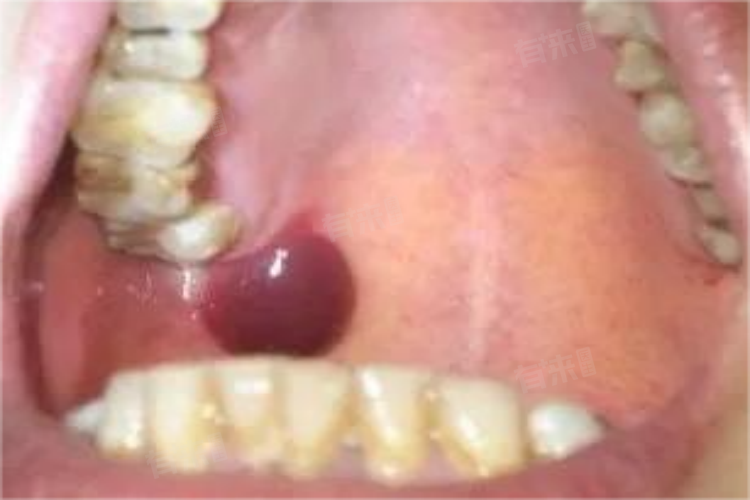

- 口腔科:优先排查口腔疾病,如根尖周炎引发的上颚肿胀、腭部溃疡或黏液腺囊肿。医生会检查牙齿有无龋坏、叩痛,观察上颚黏膜是否有充血、溃疡或肿物,判断肿痛是否与牙齿或口腔黏膜病变相关。

- 口腔颌面外科:当上颚肿痛伴明显肿胀或触及硬块,可能是颌骨囊肿、肿瘤或感染,颌面外科医生会评估病变范围,结合影像学检查判断是否需手术干预或进一步活检。